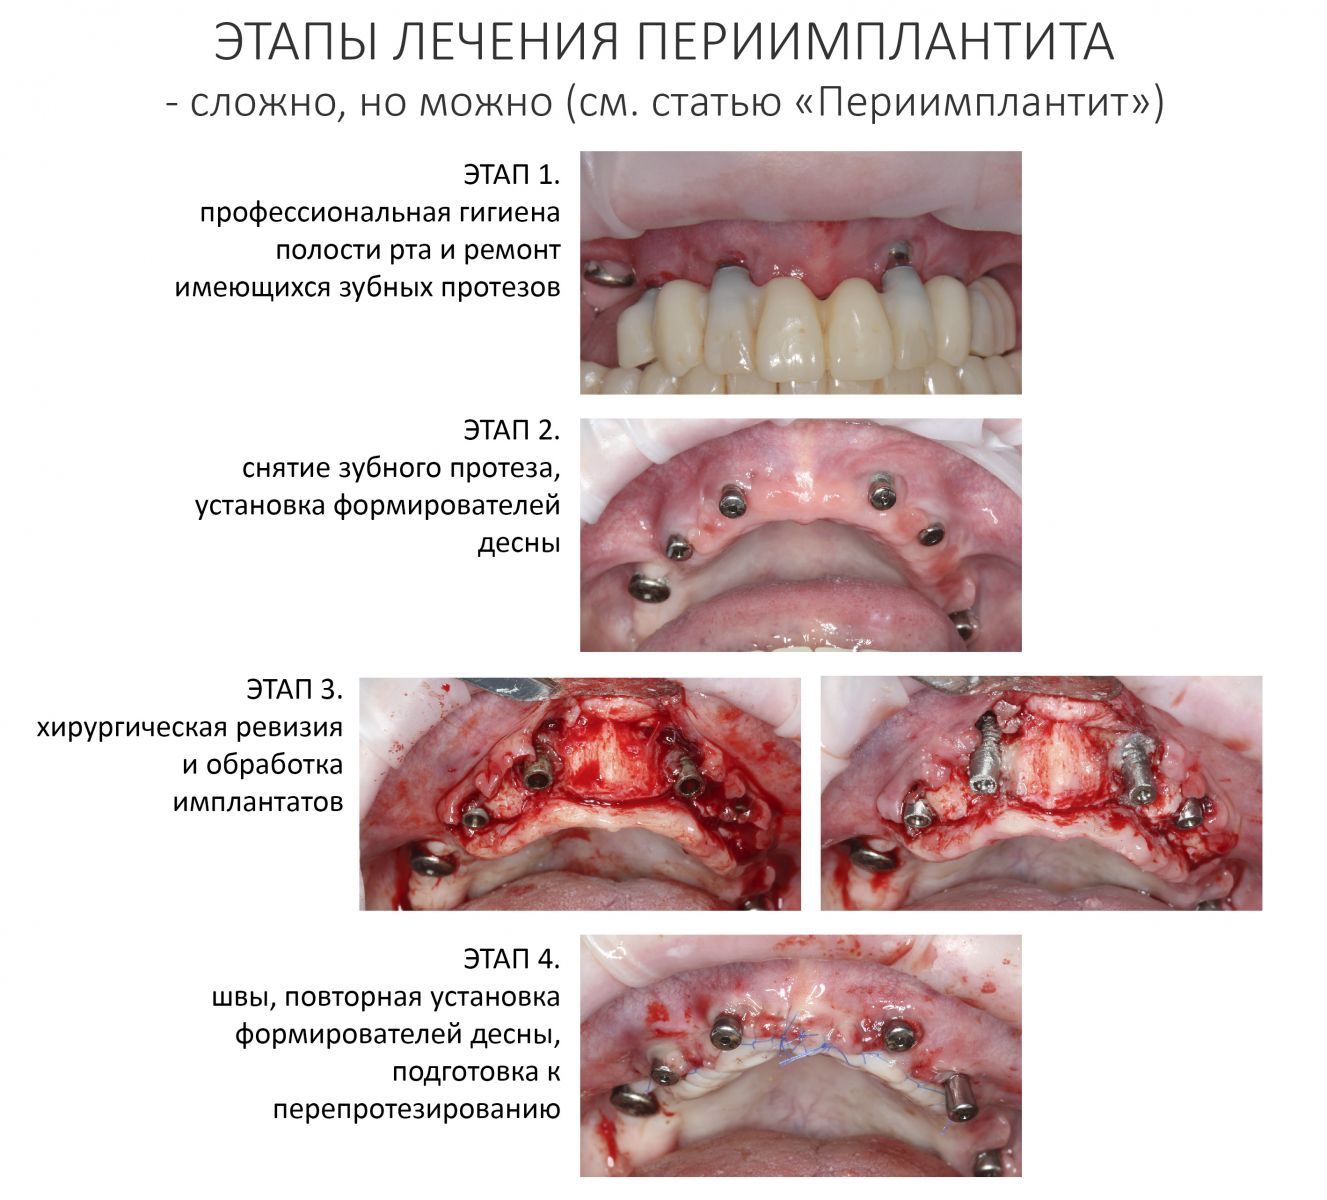

Конечно, мы решим эту проблему. В нашей клинике накоплен достаточный опыт лечения периимплантитов и ревизий давно установленных имплантатов. В конце концов, протез можно снова заменить на временный, некоторые имплантаты поменять, а оставшиеся привести всё в порядок.